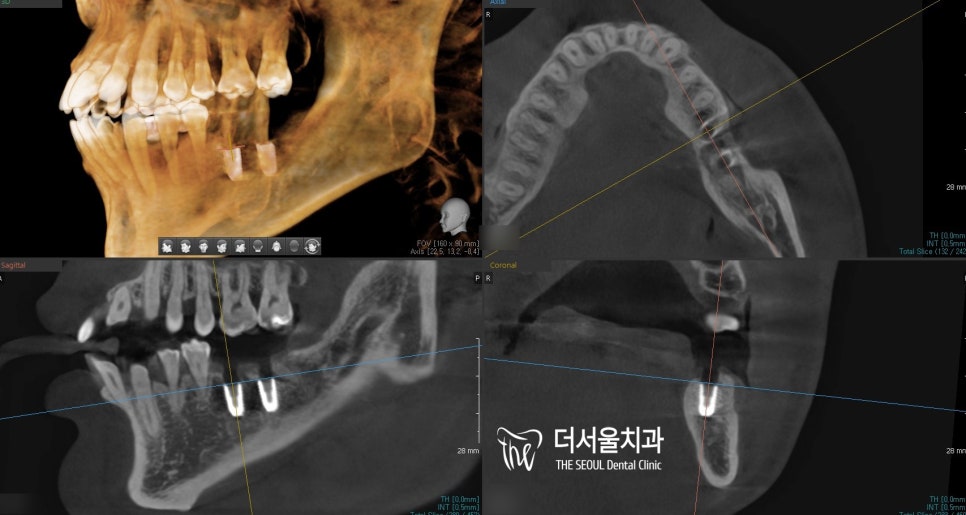

단, 골소실이 어느 정도 있었기에

뼈이식을 해야 되는 것은 아닐까,

하치조 신경과 거리는 가깝지 않을지

3D CT를 촬영하여

상태를 먼저 파악했습니다.

다행스럽게도 하치조 신경과의 거리는

문제가 될 정도로 가깝지 않았기에

뼈이식없이 심을 수 있었습니다.

그러나 모란역치과 의료진은

좀 더 정확한 진단과

좋은 결과를 드릴 수 있도록

컴퓨터 분석 프로그램을 통하여

체크를 했는데요.

표시된 것처럼 신경은 더 밑으로 지나고 있어

심는데 큰 무리없이 해드릴 수 있었습니다.